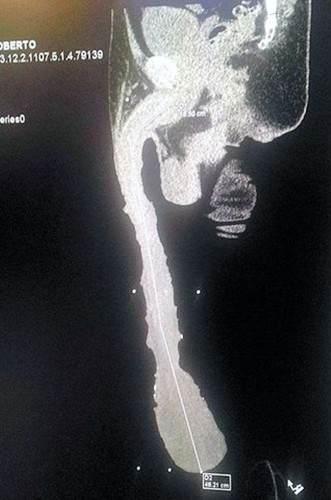

Coahuila eyaletinin kuzey doğusundaki Saltillo kentinde yaşayan Cabrara, tıbbi muayene olup, iddiasına inanmayanlar için x-ray’den bile geçmiş.